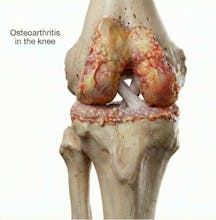

Natomy AI creates high-quality, medically accurate images and videos of human anatomy. Start with image-to-image: upload any low-quality photo, real image, or animation, and Natomy transforms it into an ultra-realistic anatomical visual. Unlike other AI tools that get anatomy wrong, Natomy is accurate every time—and fully editable by simply highlighting what you want changed and describing the update. Text-to-video launches in 2 weeks.